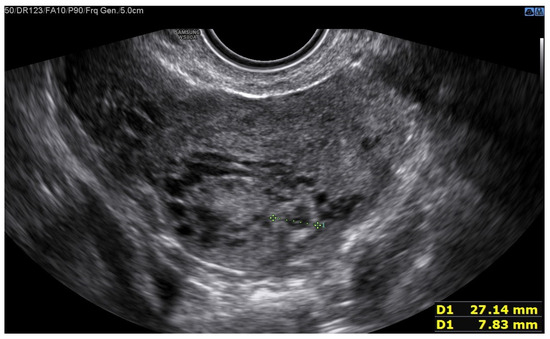

A 25-year-old woman, with a history of left tubal laparoscopic salpingectomy for an ectopic pregnancy, sought medical attention at the hospital’s emergency department after an episode of vaginal bleeding at 5 + 6 weeks of amenorrhea. At Day-1, her β-hCG was 2528 mUI/mL but a transvaginal ultrasound scan (TVUS) showed no clear evidence of pregnancy. Therefore, the patient was admitted with a diagnosis of pregnancy of unknown location (PUL). Upon admission, the patient was clinically and hemodynamically stable and did not report any pain or active bleeding. Serial measurement of her β-hCG in the following days was consistent with a suboptimal growth (3696 at Day-2, 5898 at Day-4, 10,984 at Day-7). Repeated TVUSs failed to show sure evidence of pregnancy until Day-7, when an intramural vascularized mass of 27 × 8 × 20 mm, with a gestational sac of 7 mm, a yolk sac and a 2 mm embryo with a heartbeat, was detected (Figure 1). Pelvic nuclear magnetic resonance (NMR) performed at Day-7 confirmed the presence of an intramyometrial T2-hypointense signal alteration of 20 mm in the right cornual area, surrounded by ectasic vessels, suggestive of interstitial pregnancy (Figure 2). After thorough counselling, a conservative management was proposed and accepted by the patient. The patient was administered a single oral dose of mifepristone 600 mg in combination with multidose systemic MTX 72 mg on days 0, 2, 4 and 6 from diagnosis. Follow-up by TVUS and β-hCG measurement was carried out. By Day-15, β-hCG reached a plateau and started reducing. A TVUS confirmed the termination of the pregnancy by involution of the gestational sac and the presence of the embryo with the disappearance of the fetal heartbeat. After 22 days from treatment, while the pregnancy was disappearing, in the same site, TVUS showed the appearance of a myometrial tubular hypoechoic region of 37 × 38 mm with an intensely vascular and multidirectional flow. Spectral Doppler ultrasound showed a low-resistance, high-velocity (peak systolic velocity of 128 cm/s) flow pattern, suggestive of uterine arteriovenous malformation (AVM) in the location of the previous interstitial pregnancy (Figure 3). The patient remained asymptomatic. To avoid menstrual bleeding and minimize the risk of metrorrhagia, a depot 3.75 mg shot of a GnRH analogue was administered every 28 days for 4 months. Considering the desire to preserve the fertility of the patient, the absence of guidelines for the treatment of AVM and the good results presented in the literature on uterine artery embolization as a conservative treatment, we performed a right uterine artery embolization, with sonographic resolution of the AVM within 3 months (Figure 4). We accessed the right common femoral artery and a 5-Fr introducing an angiographic sheath was placed. A 5-Fr Cobra catheter (Cook, Bloomington, IN, USA) was used to perform nonselective angiograms of the internal iliac arteries in order to achieve a general understanding of the vascular anatomy; the right internal iliac artery was selected after creating a Waltman loop with the Cobra catheter. The right uterine artery was selected using a microcatheter ranging from 2.0 to 2.4 Fr. As embolic materials, polyvinyl alcohol particles were used (Contour; Boston Scientific, Cork, Ireland). The rescue treatment had no complications. We present an unpublished case of interstitial pregnancy in a hemodynamically stable woman at an early gestational age successfully treated with medical therapy using MTX and mifepristone, who developed a peculiar complication.

Figure 3. Arteriovenous malformation (AVM).